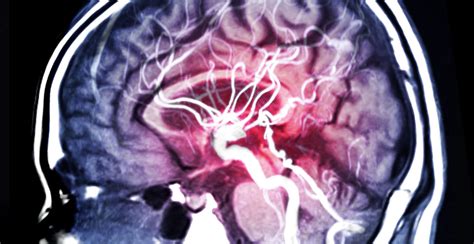

Cerebral haemorrhage, a type of stroke caused by bleeding in the brain, is a medical emergency that requires immediate attention. The road to recovery after a cerebral haemorrhage can be long and challenging, but with the right approach and support, many individuals can make significant progress. This blog post will delve into the various aspects of cerebral haemorrhage recovery, including understanding the condition, the recovery process, rehabilitation strategies, and the importance of support systems.

A cerebral haemorrhage occurs when a blood vessel in the brain ruptures, leading to bleeding into or around the brain. This can cause damage to brain tissue and disrupt normal brain function. The symptoms of a cerebral haemorrhage can vary widely depending on the location and extent of the bleeding. Common symptoms include: